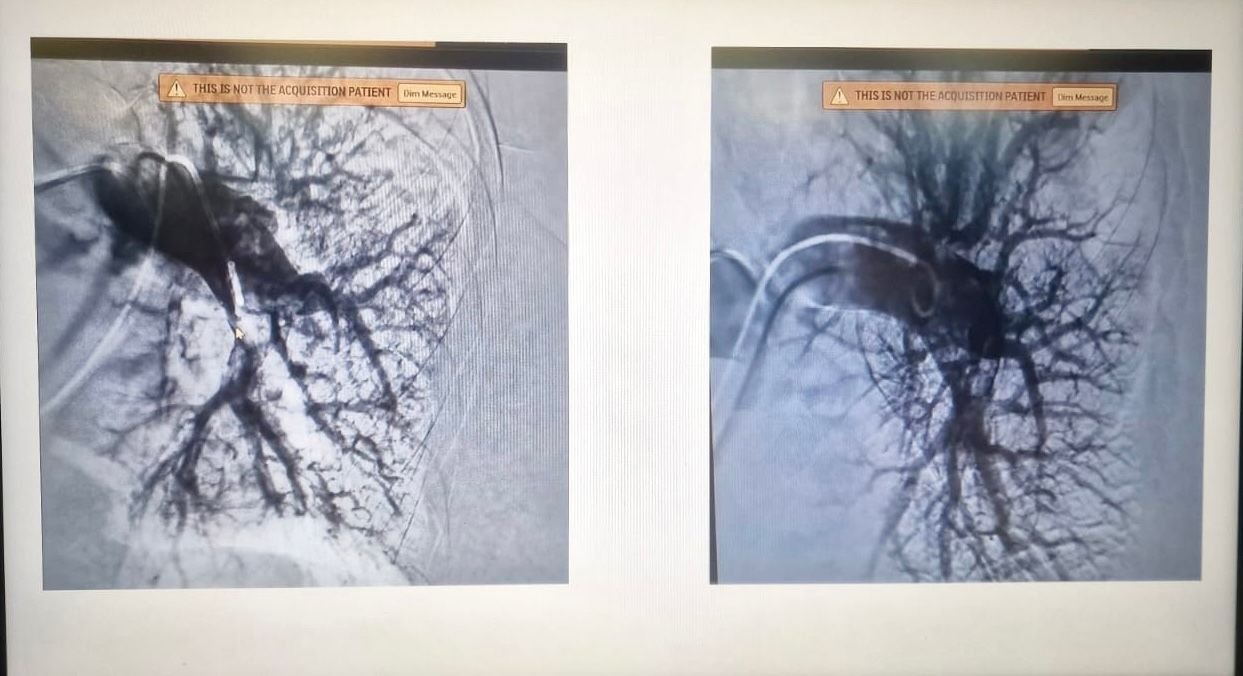

A közlemény szerint a 46 éves férfi pácienst egy iszkémiás stroke-ot követően utalták be a kórházba, és az intervenciós radiológiai osztályon trombektómiával (a vérrög eltávolítása) kezelték, de később agyödéma alakult ki nála, ezért sürgősen átszállították az idegsebészetre, ahol dekompresszív craniectomián (koponyacsont egy részének eltávolítása) esett át. A kórházi kezelés során a betegnél tüdőembólia is kialakult, egy vérrög az alsó végtagokból a vérkeringésbe került, elzárva a szívből a tüdőbe vért szállító egyik eret.

Ezekben az esetekben a klasszikus kezelés a szisztémás trombolízis, egy orvosi eljárás, amelyet az ereket elzáró vérrögök feloldására használnak, hogy megakadályozzák az érintett szövetek vagy szervek károsodását. Ebben az esetben azonban a stroke és a műtét miatt a betegnek abszolút ellenjavallott volt ez előbbi eljárás.

A szakorvosokból álló bizottság úgy döntött, hogy január 16-án katéteres trombektómiát hajtanak végre egy olyan eszközzel, amely lehetővé teszi a vérrög szelektív leszívását, és korlátozza a vérveszteséget. „A műtét jól sikerült, a beteg állapota kedvezően alakult, és hazaengedték” – áll az egészségügyi intézmény sajtóközleményében. A műtétet végző csapat tagjai: dr. Mihnea Traian Nichita-Brendea kardiológus, dr. Sebastian Boancă radiológus, dr. Mester András kardiológus és dr. Ștefan Pataki orvos volt.